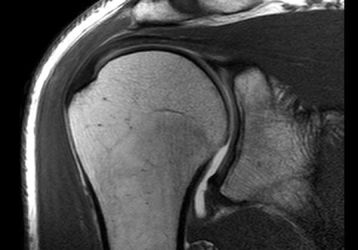

МРТ плечевого сустава — как делают и расшифровка результатов

Что показывает МРТ плечевого сустава, как расшифровать результаты. Описание проведения процедуры и противопоказания к диагностике.